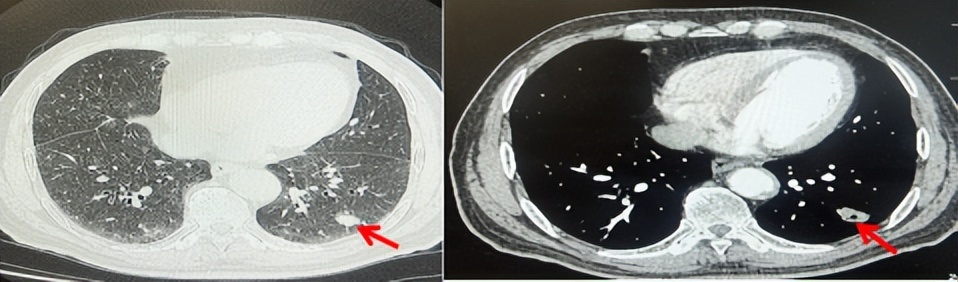

69岁男性,无糖尿病、高血压、心脏病等基础疾病,无吸烟、饮酒史,无肿瘤家族史。2023.06.07行胸部CT检查:右肺上叶胸膜下见肿物影,大小约33mm×22mm,边缘可见分叶,考虑恶性病变可能性大,双肺间质改变(如图1)。2023.06.14行“单孔胸腔镜下右肺上叶切除、肺门及纵隔淋巴结清扫、胸膜粘连松解术”;术后病理:(右肺上叶)腺癌(低分化,实体型占60%,不良腺体占40%),局灶伴神经内分泌标记表达(CD56、Syn),可见STAS及胸膜侵犯,未见确切神经侵犯及脉管内癌栓;(气管切缘)净;(淋巴结)未见转移癌0/26(2组0/2;4组0/6;7组0/2;对侧7组0/8;10组0/2;11组0/3;12组0/2;13组0/1)。术后分期pT2aN0M0 IB期,术后NGS基因检测:无驱动基因突变,PD-L1(22C3)TPS<1%。术后定期复查。

图1:患者手术前(2023.06)胸部CT肺窗及纵隔窗

图2:患者胸膜及肋骨转移(2024.11)胸部CT肺窗、纵隔窗及骨窗